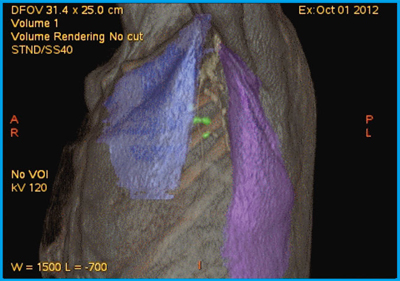

●症例8:CABG後胸痛のMyocardial perfusion Tl scintigraphy

症例8は,2年前にCABGを施行した症例で,心筋血流シンチグラフィを撮像したところ下後壁に虚血が認められたが,責任血管がグラフトなのか,native RCAなのかの判別が困難であった。そこで,SPECT/CT-造影CTフュージョンを行うと,血流低下領域が紫色で表示され,#4AVの血管領域が責任血管であることが一目でわかり,非常に有用な情報を得ることができた(図12)。

図12 症例8:CABG後胸痛のSPECT/CT-造影CTフュージョン3D画像